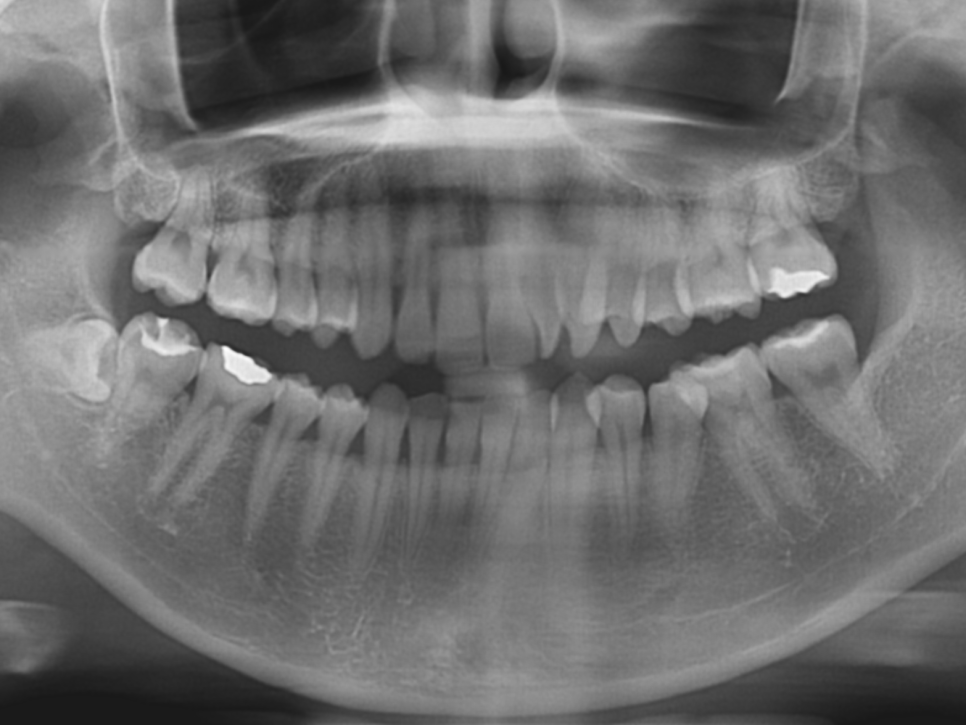

하지만 이번 환자분께서는 송곳니의 문제가 아니라

측절치의 문제이기 때문에 부분 앞니교정으로도

충분히 가능한 케이스에요.

환자분의 치아를 진단한 결과

/90도 회전 측절치 개선

/전치부 배열을 위한 앞니교정